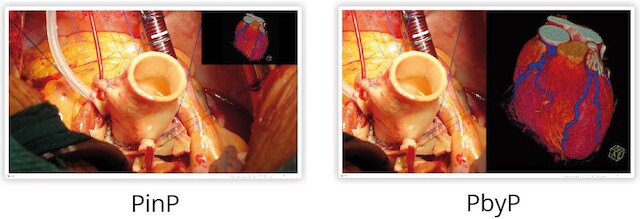

全世界的人均寿命都在不断延长,因此对病人温和的微创手术变得越来越重要。手术的成功在很大程度上取决于细致的成像流程,它能使外科医生尽可能准确地协调手眼动作。因此,除了高分辨率监视器外,3D 成像技术也进入了手术室。逼真的光学景深成像可实现更精确、更快速的干预。到目前为止,在手术室设备推车上灵活使用的 4K UHD 3D 技术仅限于尺寸较小的显示器,最大尺寸为 32 英寸,这只能显示图像的一小部分。而 55 英寸的较大对角线尺寸屏幕则只能永久安装在墙壁和天花板支架上。